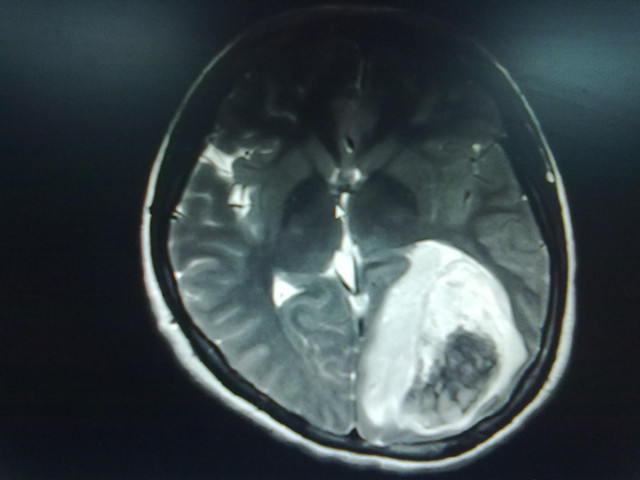

经紧急术前准备,患者很快送进了手术室,麻醉插管、生命监测、消毒铺巾等有序展开。打开患者颅骨可见脑膜似硬皮球样坚硬,脑膜张力大、脑压极高;切开脑膜后,见大面积脑组织受肿瘤侵犯,大量变性脑组织及肿瘤组织外涌,肿瘤大小约80×70×70MM3,肿瘤边界不清,血供丰富。经缓慢减压,清除血肿,仔细分离肿瘤,成功切除全部脑肿瘤组织及血肿。术后病理报告:间变型星形胶原细胞瘤(Ⅲ级)。

术前影像学改变